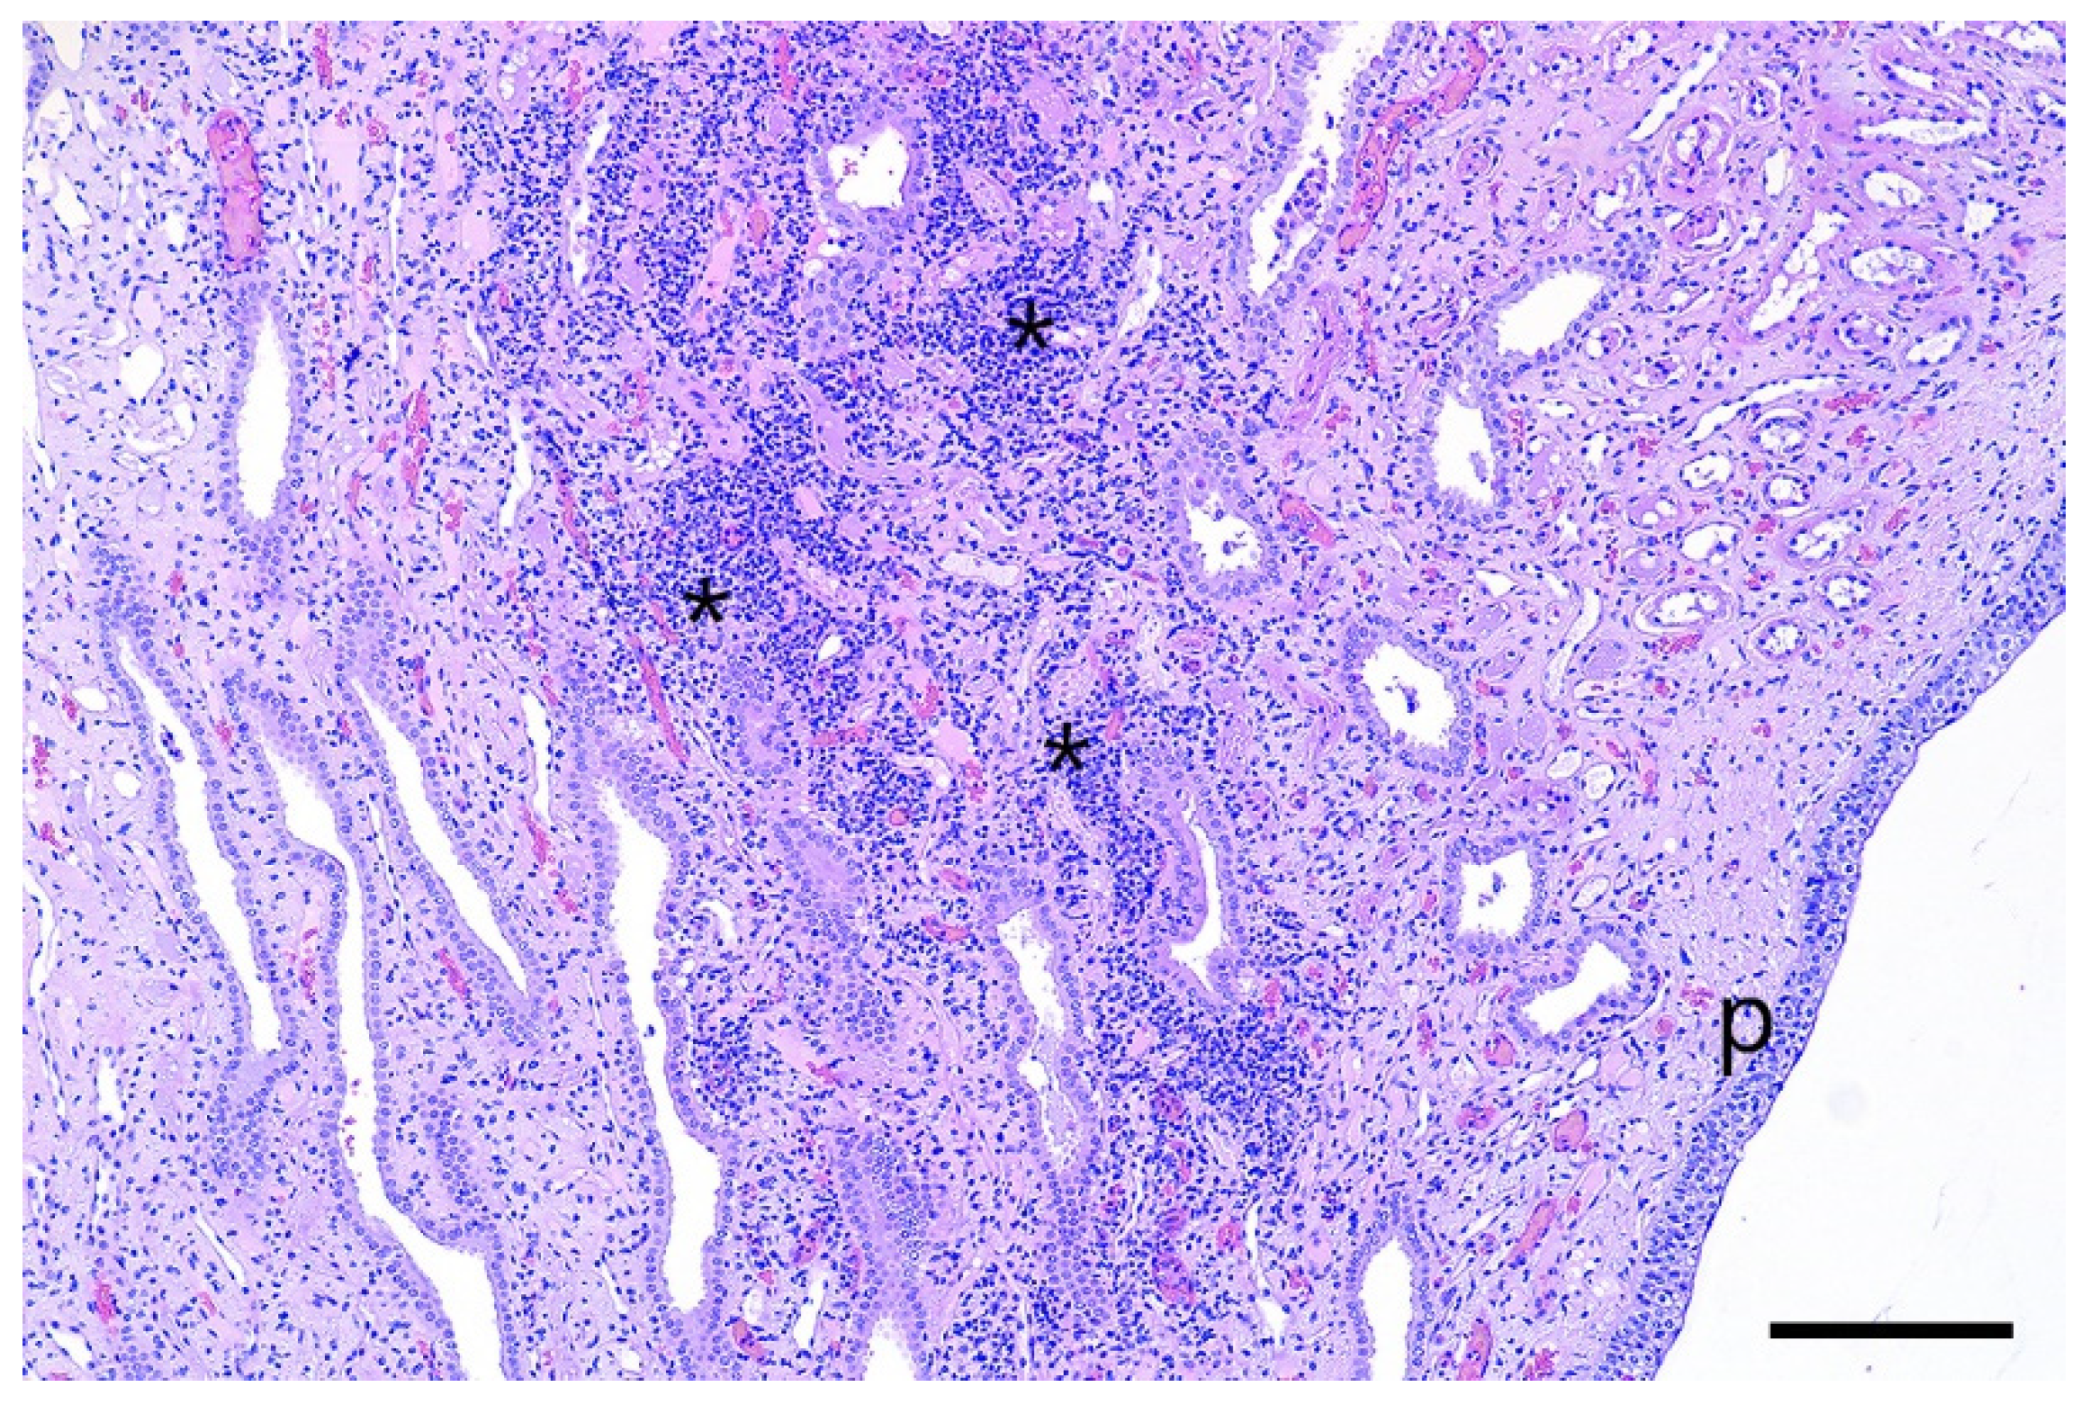

In the infected animals, different grades of focal or multifocal, predominantly lymphocytic tubulo-interstitial nephritis were detected in the course of the histologic examination (Figure 5). The inflammatory response was more present in the renal medulla, affecting the collecting ducts. No tubular epithelial alterations were seen, and no spirochaetal organisms could be visualized by Warthin–Starry silver staining. The liver and uterus did not show any relevant histologic alterations.

Multifocal tubulo-interstitial nephritis is a common finding in pigs affected by Leptospira, especially by Leptospira interrogans serovar Pomona. This condition is characterized by the presence of white spots in the parenchyma of the kidneys [30,31], which was not observed in this study. Michna and Campbell (1969) and Scanziani et al. (1989) [32,33] reported that leptospires are not always detectable in the kidneys of Leptospira-infected pigs showing interstitial nephritis, as described in the present case. The histologic detection of tubulo-interstitial nephritis without fibrosis indicates a slight subacute tubulary damage of the affected kidneys. It can be speculated that this was caused by the leptospires, as the lesions were only found in the kidneys of inoculated animals.

Figure 5. Severe tubulo-interstitial nephritis (asterisks) near to the renal pelvis (p) of an infected gilt. No tubular alterations are seen. Microphoto, H&E, bar= 200 µm.